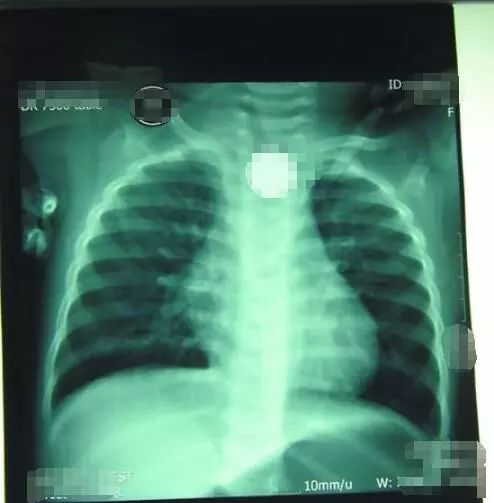

今年1月,郧西8岁女童反复咳嗽,太和医院专家检查时,发现其肺部有像吹哨子一样的声音。原来一支笔头卡在了女童的支气管中,且已引起反复炎症。最终医生在女童胸壁开了3个孔才将异物取出。

片子中可以看到女童支气管被笔帽卡住